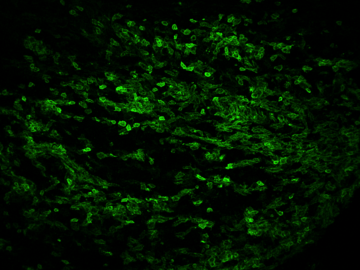

Striking Laboratory Data Images

Laboratory Data Gallery

Universe of the brain